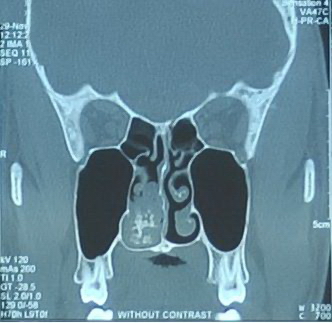

Nasal Polyp With Heterotopic Bone Formation (Osseous Metaplasia): A Case Report

Osseous metaplasia is defined by the presence of heterotopic normal bone tissue in a soft tissue. Metaplastic ossification is a rare event in nasal polyps. The authors describe a rare case of bone formation in nasal polyp of a 28-year-old man with chronic right-sided nasal obstruction without history of trauma or allergy symptoms. To our knowledge, this finding has been reported in a few cases in the English medical literature.